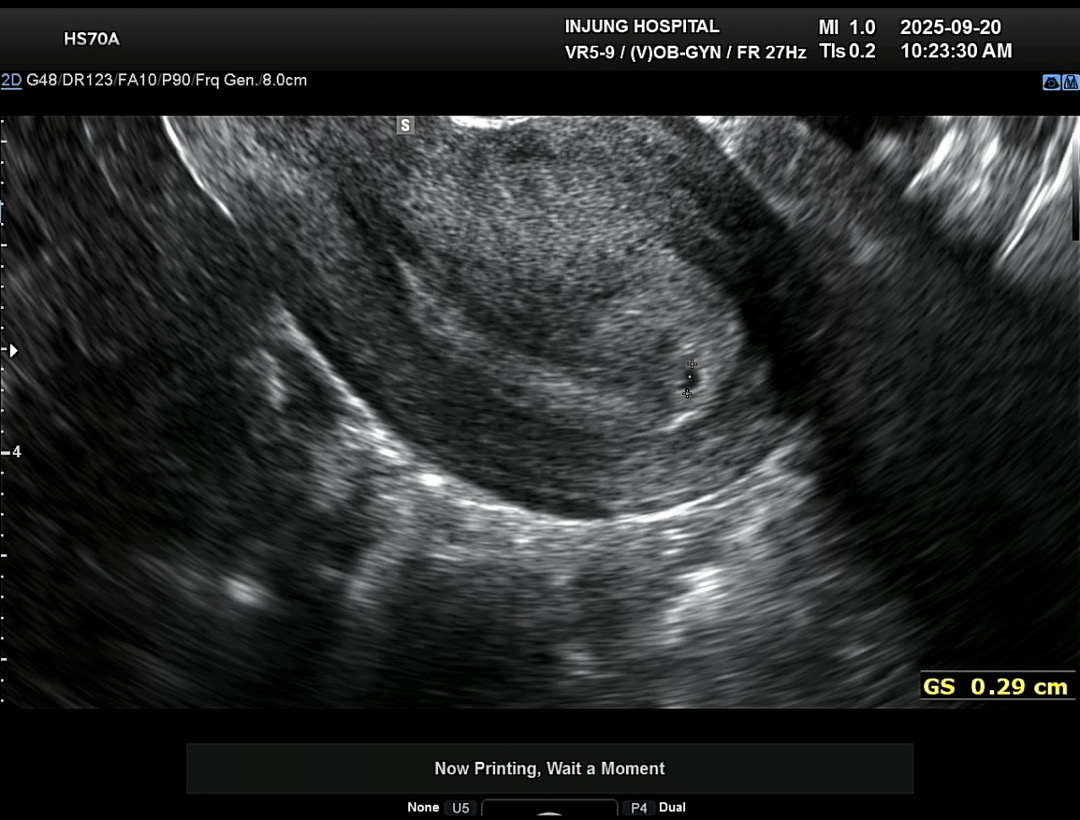

네이버 주수로는 6주 1일인데 자연임신이라 착상이 늦은건지 착상된지 일주일도 안되어 보인다고 하시더라구요🥺 사실 원포 진하기가 비슷하고 역전이 안 된 것 같아서 아기집도 못 보고 올까봐 걱정됐는데, 0.29cm로 아주 쪼꼬맣고 귀엽게 집 지어놓은게 너무 기특하고 귀여워서 아기집 보고 온 것만 해도 너무 안심되네요ㅎㅎ 질정 처방 받아서 살짝 걱정은 되지만 일주일 또 잘 키워봐야겠어요❤️